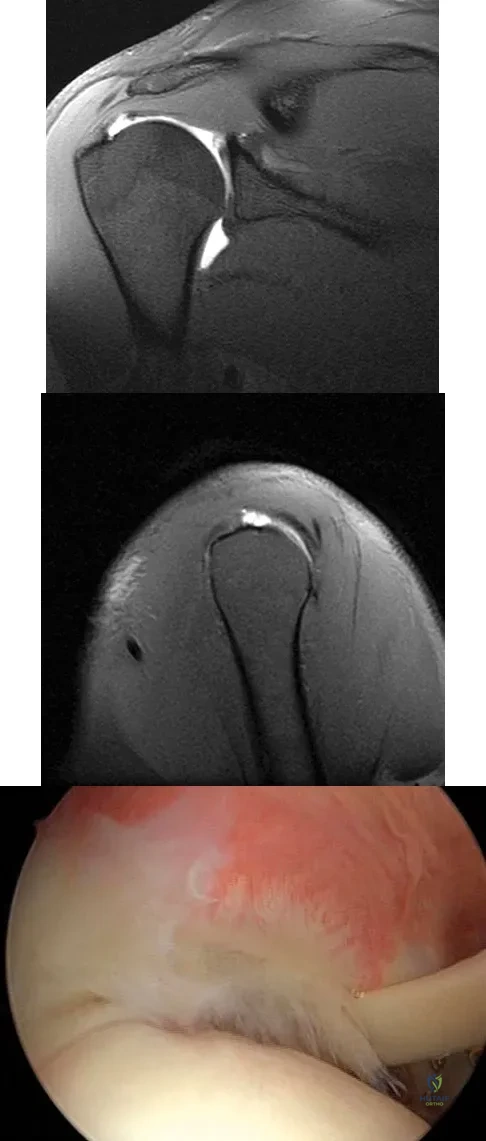

Question 30

A 25-year-old tennis player has shoulder pain and weakness to external rotation. MRI scans are shown in Figures 16a and 16b. What is the most likely cause of his weakness?

Question 45

Figures 39a and 39b show the MRI scans of a 25-year-old man with right shoulder pain. Figure 39c shows the arthroscopic view from a posterior portal in the beach chair position. What is the most likely diagnosis?

Explanation